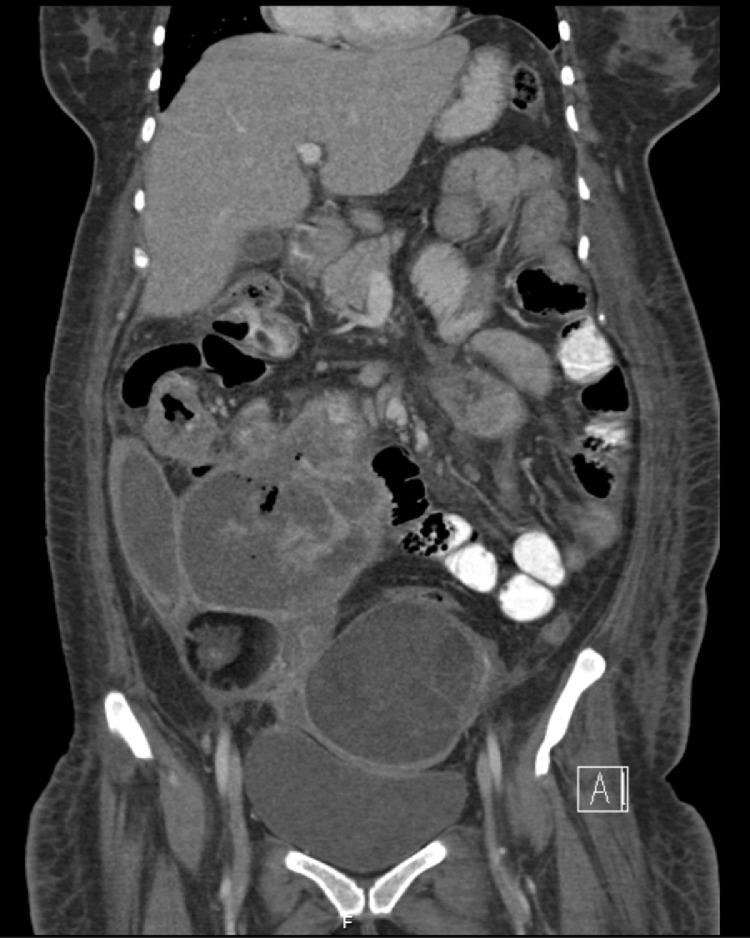

卵巢成熟性囊性畸胎瘤恶变伴小肠转移,右卵巢偶然发现浆液性囊腺瘤碰撞瘤。

Malignant degeneration of mature cystic teratoma of the ovary with small bowel metastasis incidental serous cystadenoma collision tumor of the right ovary.

Mature Cystic Ovarian Teratoma (MCOTs) are the most common benign ovarian neoplasms, representing around 20% of all ovarian neoplasms with middle age women representing the majority of patients. They usually include two germ cell layers being well differentiated and rarely they demonstrate malignant transformation with squamous cell carcinoma being the most common malignant transformation. In our case, we report an interesting case of a 45 years old lady who was unfortunate to have a MCOT with malignant degeneration and distant metastasis. We concluded that MCOT malignant degeneration is rare, however, if not caught early, mortality can be high. MCOT, Ovary, Small Bowel, Teratoma, Collision tumor.

摘要

成熟囊性卵巢畸胎瘤(MCOTs)是最常见的卵巢良性肿瘤,约占所有卵巢肿瘤的20%,患者以中年女性为主。它们通常包含两个分化良好的胚层,很少发生恶变,其中鳞状细胞癌是最常见的恶变类型。在我们的病例中,我们报告了一例有趣的病例,一名45岁女性不幸患有发生恶性变和远处转移的成熟囊性卵巢畸胎瘤。我们得出结论,成熟囊性卵巢畸胎瘤恶性变很少见,然而,如果不及早发现,死亡率可能很高。成熟囊性卵巢畸胎瘤、卵巢、小肠、畸胎瘤、碰撞瘤。